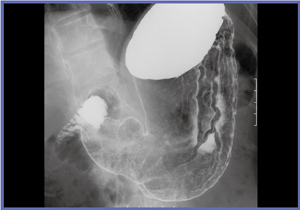

FPD装置1号機は,透視が見えにくい状態で撮影されたが,非常に精細な画像を得ることができた(図1,2)。偶然にも被検者が胃がんUc(表面陥凹)であったことも,評価を行う上で良い条件となった。1号機の評価は,非常にきれいに写るの一言に尽きる。透視が難しいことが大きな課題となっていたが,98年に現在の透視技術の完成に至った。

![]() 図2 FPD装置1号機の撮影像 アレアが喪失した部分が広がった表層拡大型胃がん |